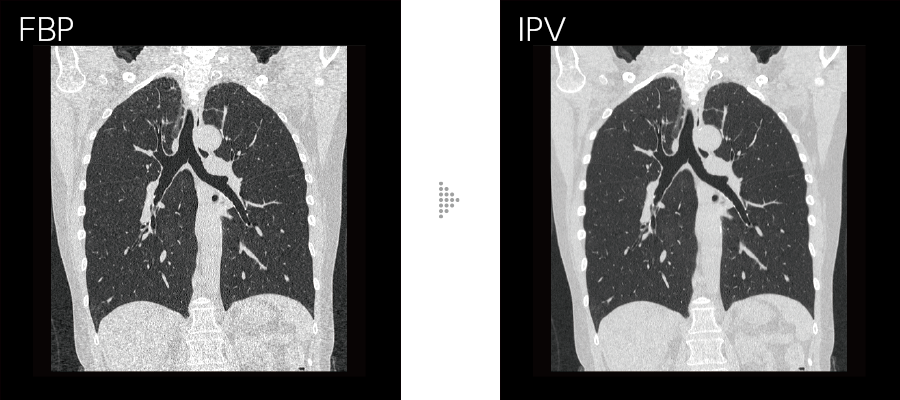

Our iterative reconstruction method, Intelli IPV, provides images that maintain their natural texture even at high noise reduction rates and their excellent visibility even at low doses, and does not require a dedicated operating room or additional hardware.

While adjusting the texture at a uniform ratio from high frequency to low frequency, the physical properties that affect visibility are made as close as FBP.